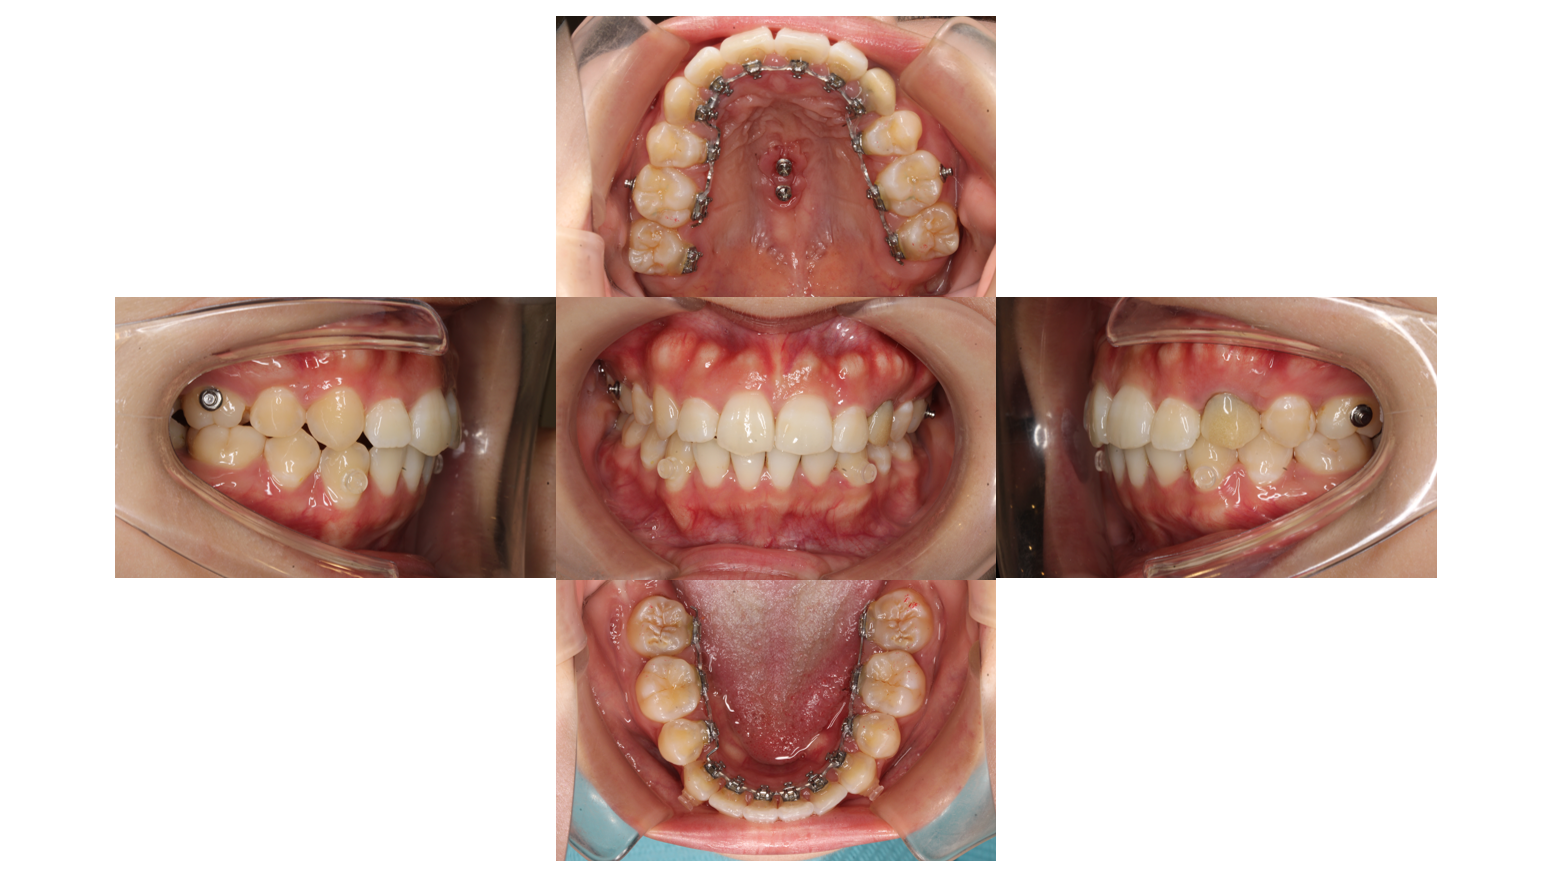

歯の凸凹を治したい(治療期間:1年11か月/通院期間22回)

After

主訴 | 【主訴】歯の凸凹を治したい 【診断・症状】上下凸凹 |

治療期間 | 1年11か月(22回) |

抜歯 | 有(上5,5)(下5,5) |

矯正の装置 | 裏側矯正(舌側矯正) |